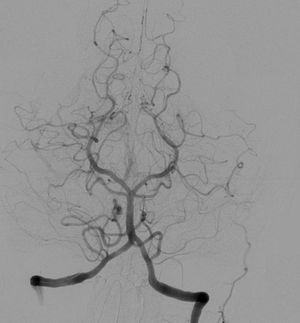

혈관 조영술은 투시술을 사용하여 심혈관계를 보는 것이다. 요오드 기반 조영제가 혈류에 주입되어 혈관을 따라 이동하는 것을 관찰한다. 액체 혈액과 혈관은 밀도가 높지 않기 때문에, X-선으로 혈관을 보기 위해 고밀도 조영제(큰 요오드 원자와 같은)가 사용된다. 혈관 조영술은 동맥류, 누출, 막힘(혈전), 새로운 혈관 성장, 카테터 및 스텐트 배치를 찾는 데 사용된다. 풍선 혈관 성형술은 종종 혈관 조영술과 함께 수행된다. X선을 연속적으로 조사하여, 텔레비전 모니터를 통해 영상을 관찰한다. 피폭량은 많아지지만, 병변에 따라 진단 및 치료에 필요하다.